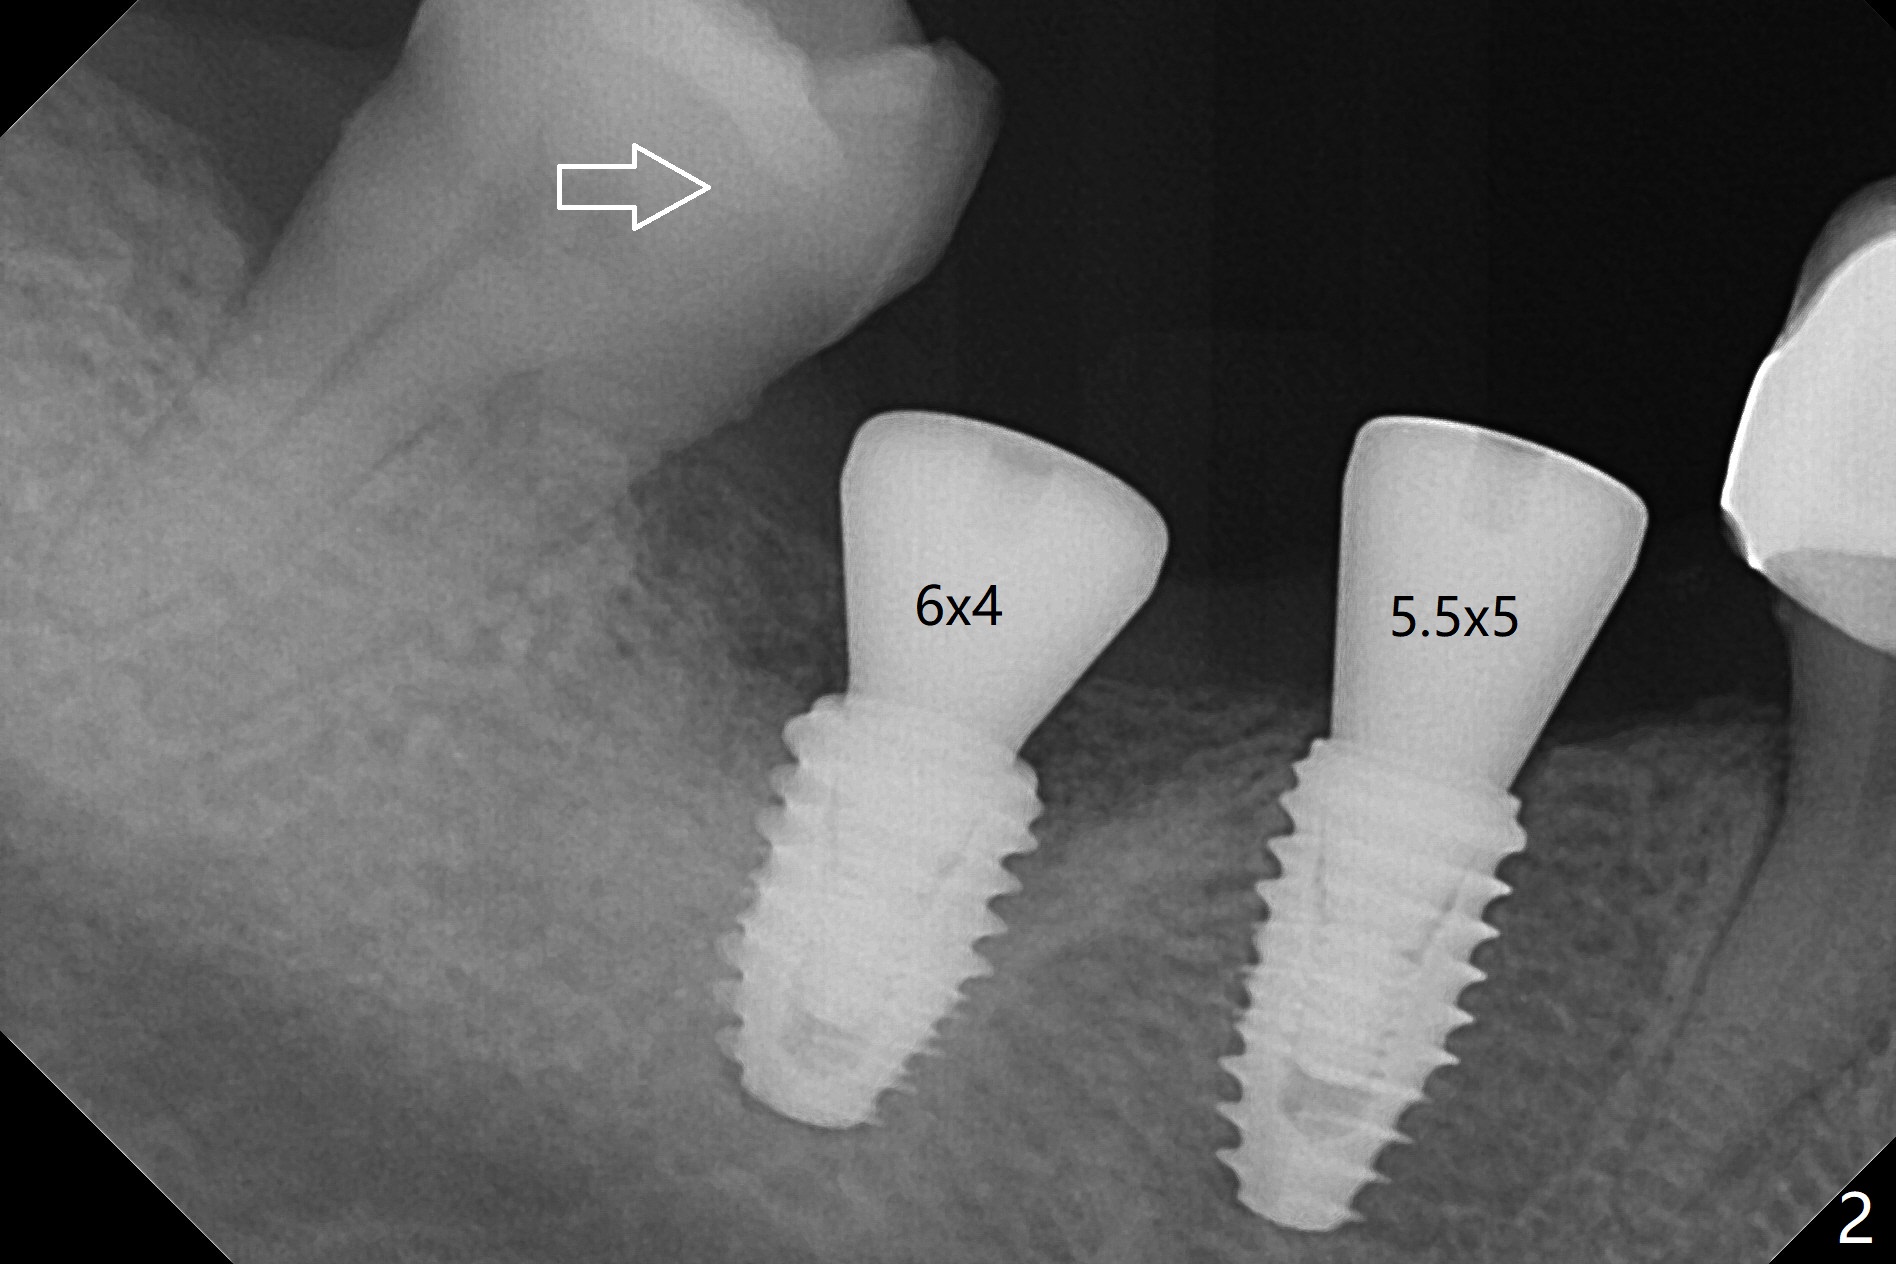

With one carpule of Xylocaine 34 mg with Epinephrine 17 mcg (infiltration) and slow osteotomy with guide, two short implants are placed at #29 and 30 painless with >45 Ncm (Fig.1). Healing abutments are placed without bony interference (Fig.2). It appears that the tooth #31 shifts mesially (Fig.2 arrow), which should be slowed down and/or corrected with early provisional. There is no bone loss 4.5 months postop (Fig.3). With placement of 4.5x4.5(3) and 5.2x4.5(4) mm abutments at #29 and 30, respectively, no limited orthodontic treatment seems to be needed. The screw at #29 becomes loose 4 months post cementation and a few days after #19 implant is loose (bruxism). In fact this is not completely true, since the abutment at #29 is incompletely seated (Fig.4). The abutment at #30 is also incompletely seated because of the vertical gap (<), probably due to mesial and distal crestal interference (*).